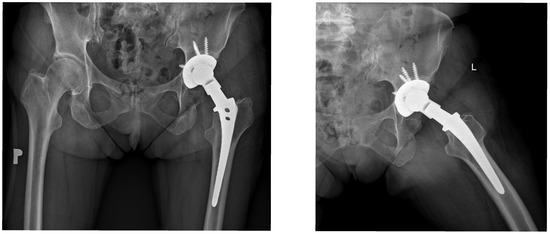

Bridging the Compatibility Gap in Revision Hip Arthroplasty with 14/16 Tapers: Long-Term Outcomes of the Bioball™ System

Purpose: Revision total hip arthroplasty (RTHA) in the presence of a well-fixed femoral stem is associated with increased risk, as stem removal often results in bone loss, prolonged operative time, and greater blood loss. This problem is particularly relevant for older implants with [...] Read more.

Purpose: Revision total hip arthroplasty (RTHA) in the presence of a well-fixed femoral stem is associated with increased risk, as stem removal often results in bone loss, prolonged operative time, and greater blood loss. This problem is particularly relevant for older implants with a 14/16 taper, which is incompatible with most modern femoral heads. The Bioball™ System, a modular head–neck adapter, allows for acetabular or head-only revision while preserving the femoral stem. This study aimed to evaluate long-term clinical and radiological outcomes of RTHA using the Bioball™ System in patients with 14/16 tapers. Methods: A total of 38 patients (23 women, 15 men; mean age 73.5 years) met the inclusion criteria. All procedures were carried out with a well-fixed femoral stem and a 14/16 taper. Revisions were limited to exchange of the acetabular component, liner, or both, avoiding stem removal. The primary indication was acetabular cup loosening (n = 29, 76.3%); liner-only exchange was performed in 9 patients (23.7%). Clinical outcomes were assessed using the modified Merle d’Aubigné and Postel (MAP) score, and radiological evaluation focused on fixation, migration, and loosening. Mean follow-up was 8.44 years. Results: Both the acetabular component and liner were replaced in 76.3% of patients, while 23.7% underwent liner and head exchange only. Longer adapter sizes were most frequently used, and a 7.5° offset adapter was applied in 57.9% of cases. The modified MAP score improved by a mean of 5.7 points (p < 0.05), and VAS pain scores decreased from 7.4 to 2.6 (p < 0.05). No radiological signs of loosening were observed at final follow-up. Conclusions: The Bioball™ System enables effective restoration of hip stability and offset without femoral stem removal, offering favorable long-term clinical and radiological outcomes in revisions involving older 14/16 tapers. Full article